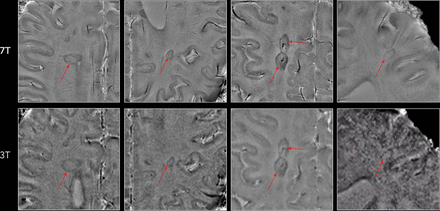

Of 98 analyzed lesions, 34 had a paramagnetic rim on 7T phase images by consensus agreement. Twenty-one of 34 lesions with a phase rim (62%) also showed a rim on T2* magnitude images (Fig 1). The intrarater and interrater agreement results are provided in Table 2. The reliability between each rater and the final consensus agreement was “almost perfect,” with a Cohen κ ranging from 0.81 to 0.91 and a pair-wise agreement ranging from 91% to 96%.

A right periventricular lesion in a 55-year-old woman with relapsing-remitting MS. A paramagnetic rim can be easily seen on 3T and 7T phase images (magnified view) as well as on the 7T T2* magnitude image (red arrows). On susceptibility images, medullary veins crossing the lesion are also prominent.